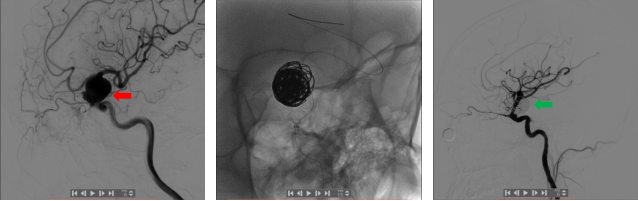

血流导向密网支架治疗动脉瘤前后对比图

新型自膨式动脉瘤瘤内栓塞系统—WEB装置治疗基底动脉尖动脉瘤前后对比图